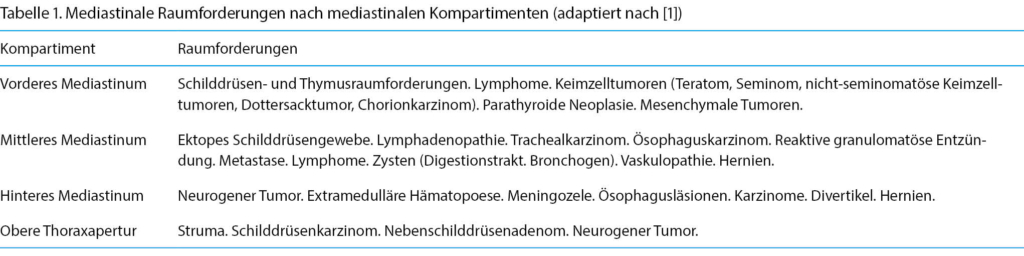

Ein 39-jähriger, nichtrauchender Mann mit einer 2-wöchigen Anamnese von zunächst in den Nacken ausstrahlenden Schulterschmerzen und im Verlauf sich verlagernder Schmerzprojektion in den vorderen oberen Brustbereich links sowie leichter Einschränkung bei vertieftem Atmen wurde initial hausärztlich abgeklärt. Bei klinisch gutem Allgemeinzustand zeigten sich auskultatorisch wenig Rasselgeräusche im linken Unterfeld und im konventionellen Thorax-Röntgenbild (Abb. 1 und 2) eine grosse Raumforderung im vorderen, linksseitigen Mediastinum. Laborchemisch fanden sich ein leicht erhöhtes CRP (33 mg/l) ohne Leukozytose sowie eine leicht erhöhte Blutsenkung.

In diesem Fall konnte bereits aus der Tumorlokalisation im vorderen Mediastinum die radiologische Differenzialdiagnose in diesem Bereich auf die 5T: teratoma, thymoma, thyroidea, terrible lymphoma, tortuous vessels) eingegrenzt werden (Tabelle 1).